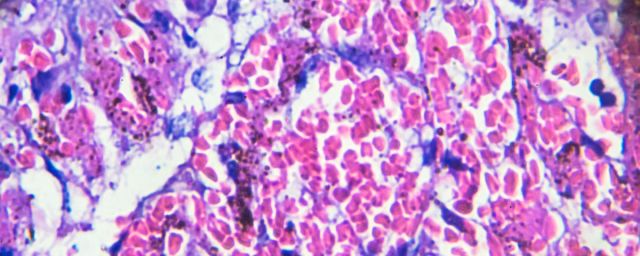

Its vascular nature means that when it gets into the lungs, it causes miniature blood clots (thrombus if only one and thrombi for many) in the lungs; when it gets into the heart, it causes lots of thrombi in the heart, when it gets into the liver, it causes thrombi in the liver, when it gets into the brain, it causes thrombi in the brain, and when it gets into the kidneys, it causes thrombi in the kidneys. All the images I linked to are from academic articles discussing Covid patients. For the lungs, I could have substituted my own CT scan–though I am not dead (yet), so I didn’t.